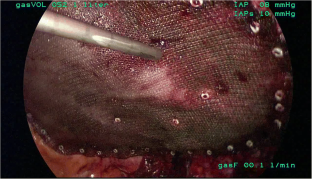

Fig. 3